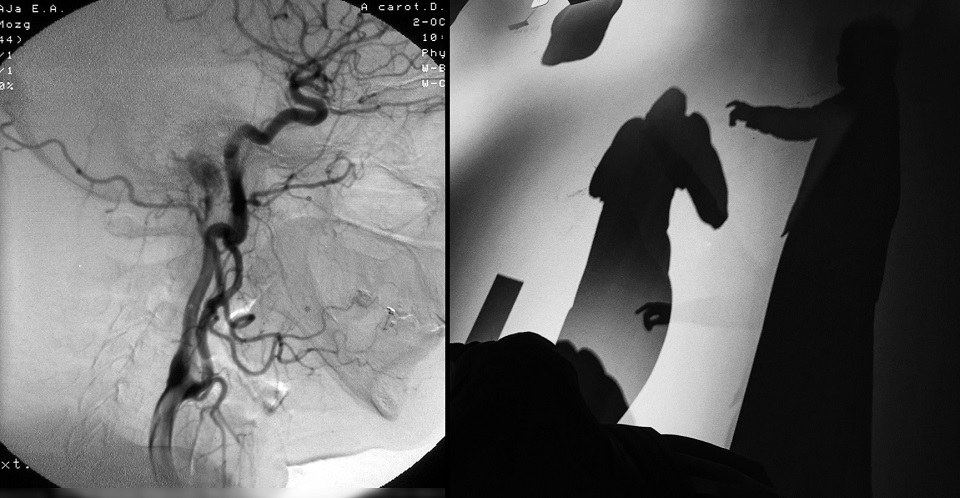

Галерея «Улица Малевича» приглашает выставку «B&W reflections». Коллажи с абстрактной черно-белой фотографией и рентген-ангиограммами авторства Алины Сафроновой будут экспонироваться с 7 июня по 4 сентября 2022 года на третьем этаже Музея современного искусства «Артмуза». Музей работает ежедневно с 11:00 до 22:00.

Серия Tree of Life посвящена теме гармонии слияния внутреннего и внешнего. Изображения кровеносной системы сопоставляются с абстрактными черно-белыми кадрами, намекая на единство всего живого и предлагая воспринимать произведение как живой механизм. Вторая серия Abstractions фокусируется на дыхании города в моменте. Через детали, отрезки, осколки, линии автор предлагает исследовать общество, как единый живой организм.